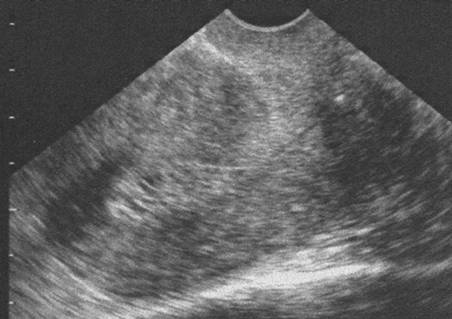

Endomètre Tamoxifène (Cliché : Dr. C. TALMANT)